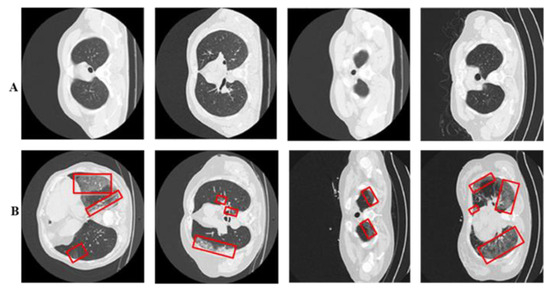

3.1. COVID-19 Infected CT Classification

3.1.1. Proposed Residual-BRNet

4.1. Dataset